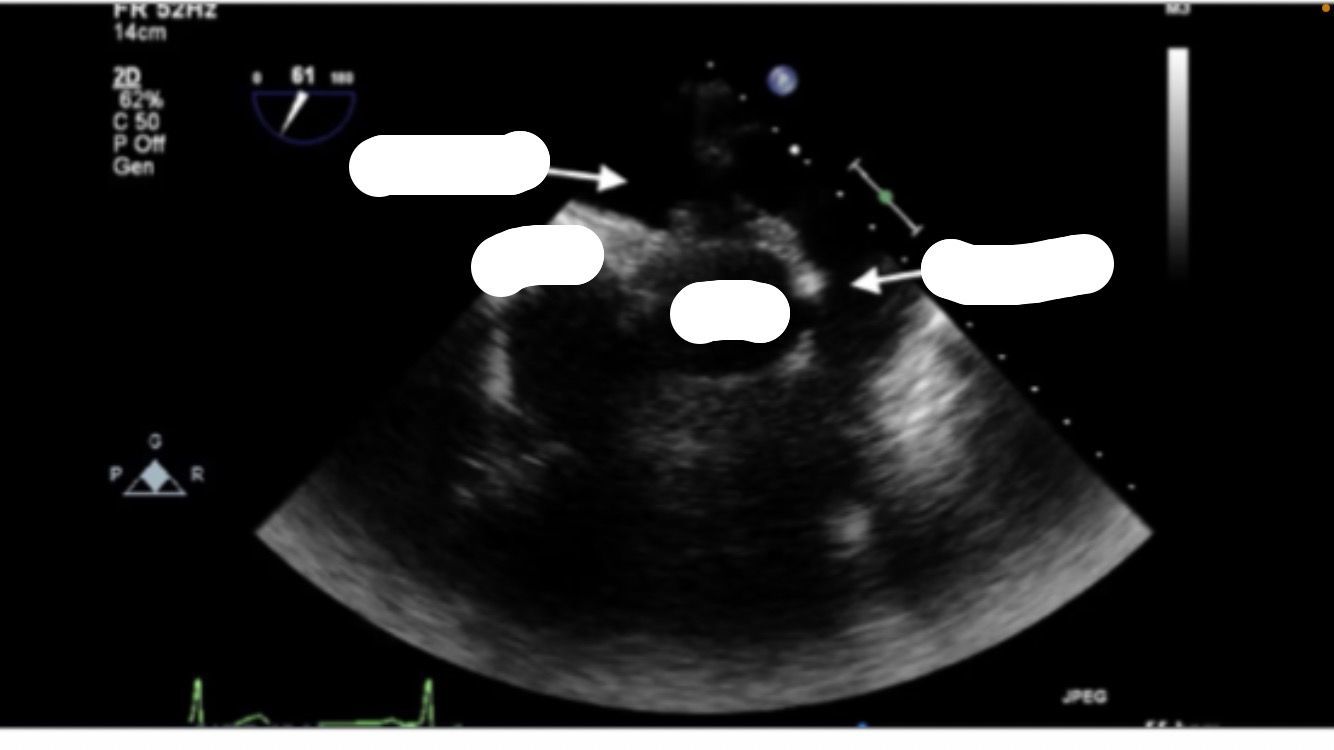

Mid esophageal RV inflow and outflow

TRICUSPID NOT MITRAL VALVE